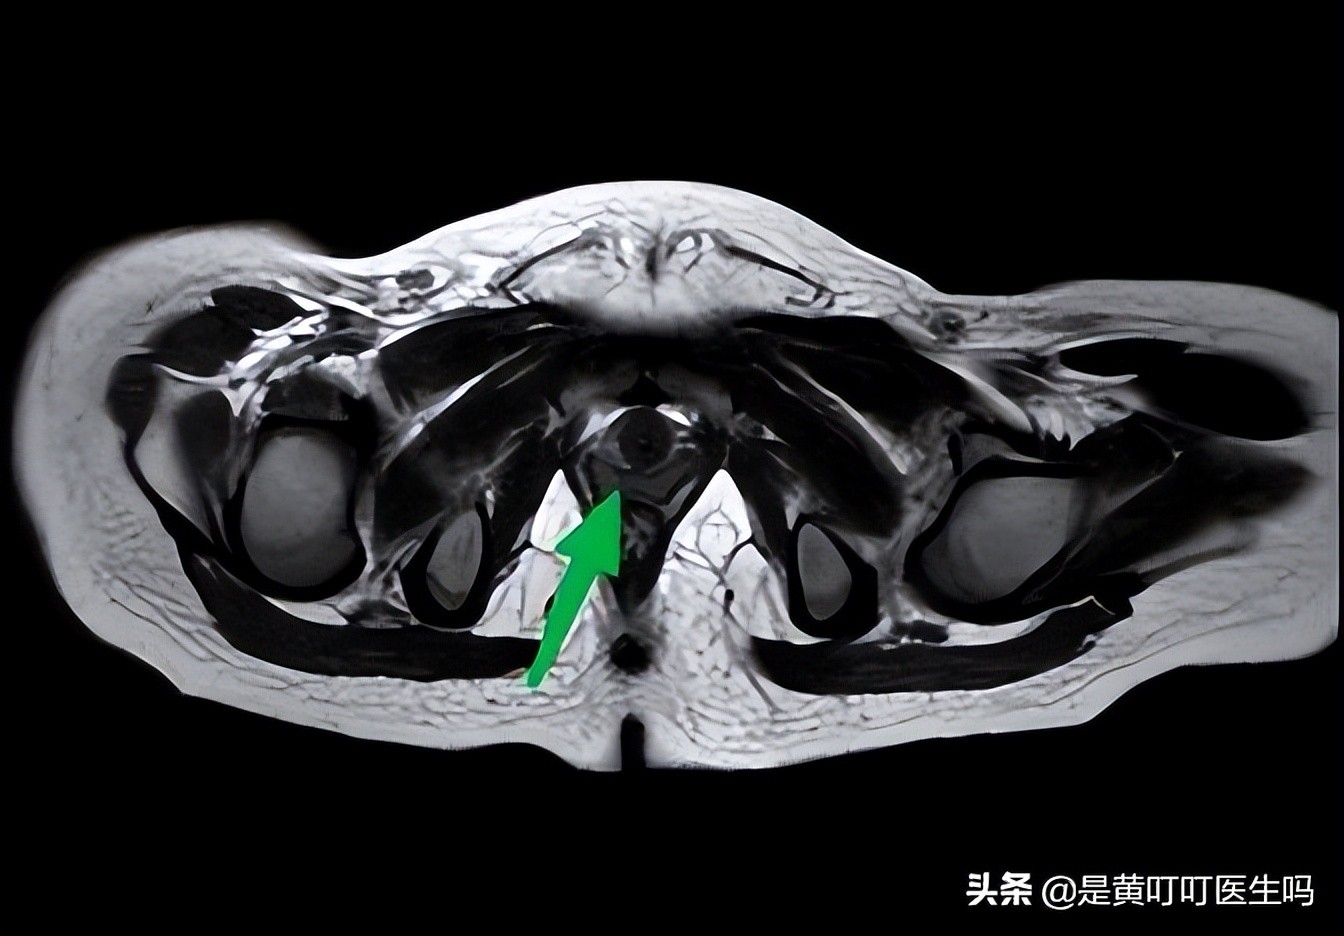

卵巢提前发育

阴道粘膜增厚(也提前发育了)